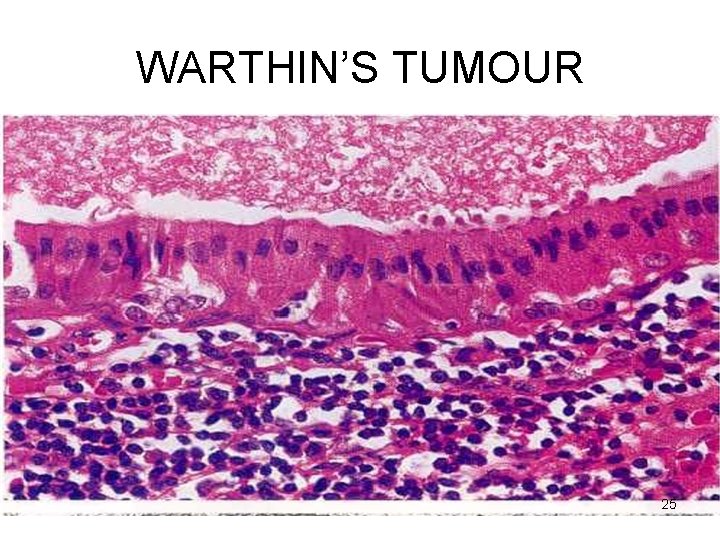

WARTHIN’S TUMOUR Microscopy Cystic spaces - Narrow / cleft-like CYSTADENOMA Lining – double-layered epithelium – infoldings PAPILLARY • Inner (lumen) – palisade of columnar cells with abundant finely granular eosinophilic cytoplasm (oncocytic) • Outer (below the first) – cuboidal / polygonal Stroma - dense lymphoid tissue (germinal centres + ) LYMPHOMATOSUM 22

WARTHIN’S TUMOUR 25